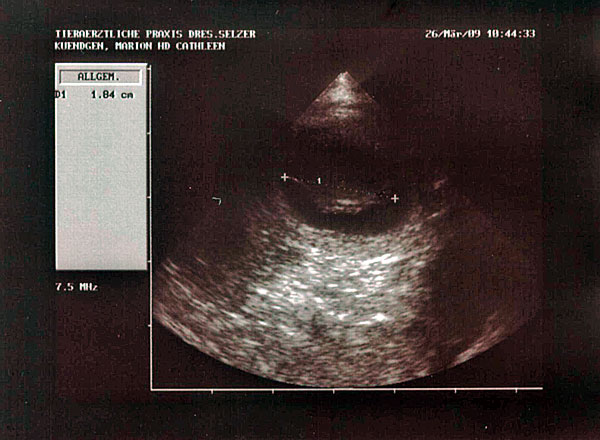

26.03.2009: Ultraschalltermin am 27. Trächtigkeitstag. Der Fötus ist schon 1,84 cm lang.